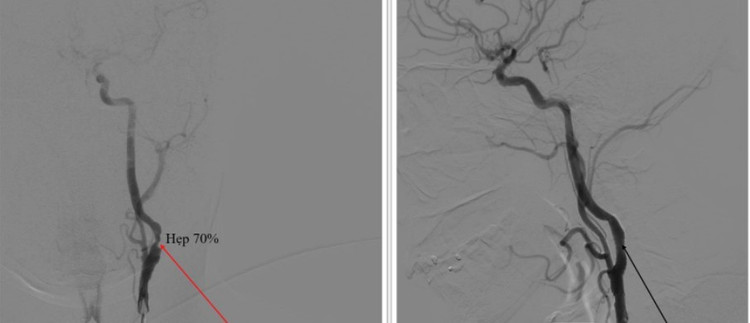

Hình ảnh tắc động mạch cảnh trước và sau can thiệp

Kíp can thiệp do ThS.BS Giáp Hùng Mạnh, Trưởng khoa Khoa thần kinh, Vật lý trị liệu – Phục hồi chức năng, Bệnh viện Bãi Cháy, cùng ê kíp đã thực hiện thành công kỹ thuật chụp mạch não, nong đoạn hẹp bằng bóng và đặt stent qua đoạn hẹp cho bệnh nhân bị hẹp 70% động mạch cảnh trong bên phải dưới sự hỗ trợ của máy DSA.